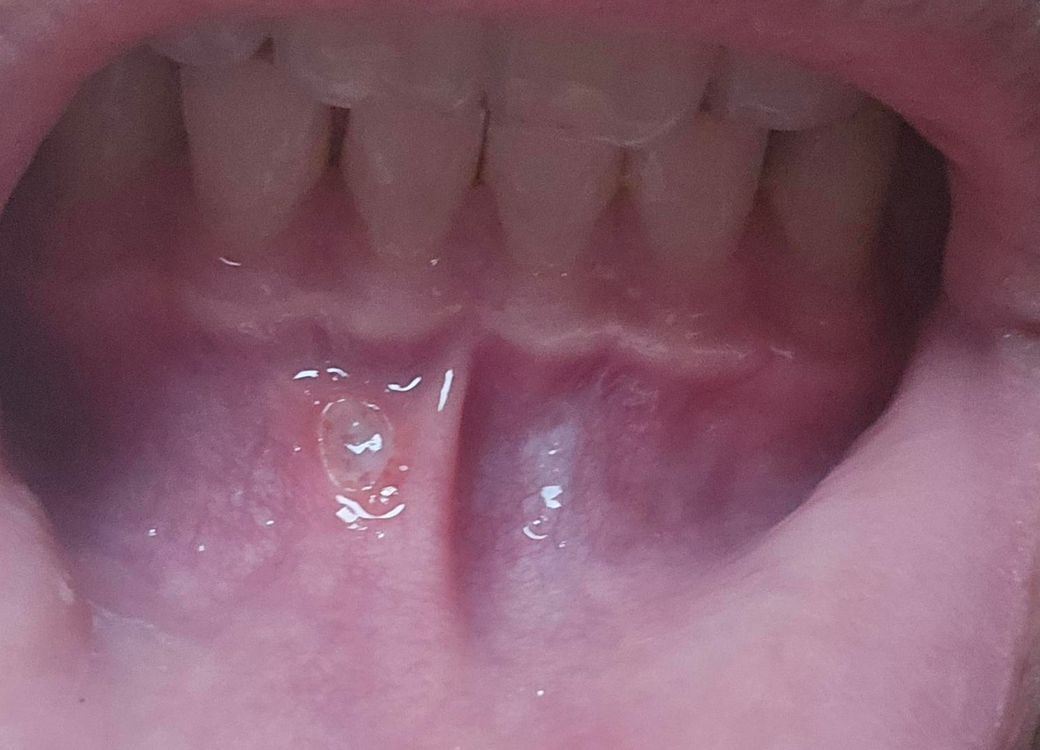

2일 전부터 계속 따끔거려서 확인 해보니 사진과 같이 움푹 파인 형상의 염증이 생겼습니다. 혹시라도 병원에 가봐야 하나요? 아니면 가그린으로 소독만 잘 하여도 괜찮나요?

• 1번 째 사진

올려주신 사진으로 미루어 구내염으로 생각됩니다.